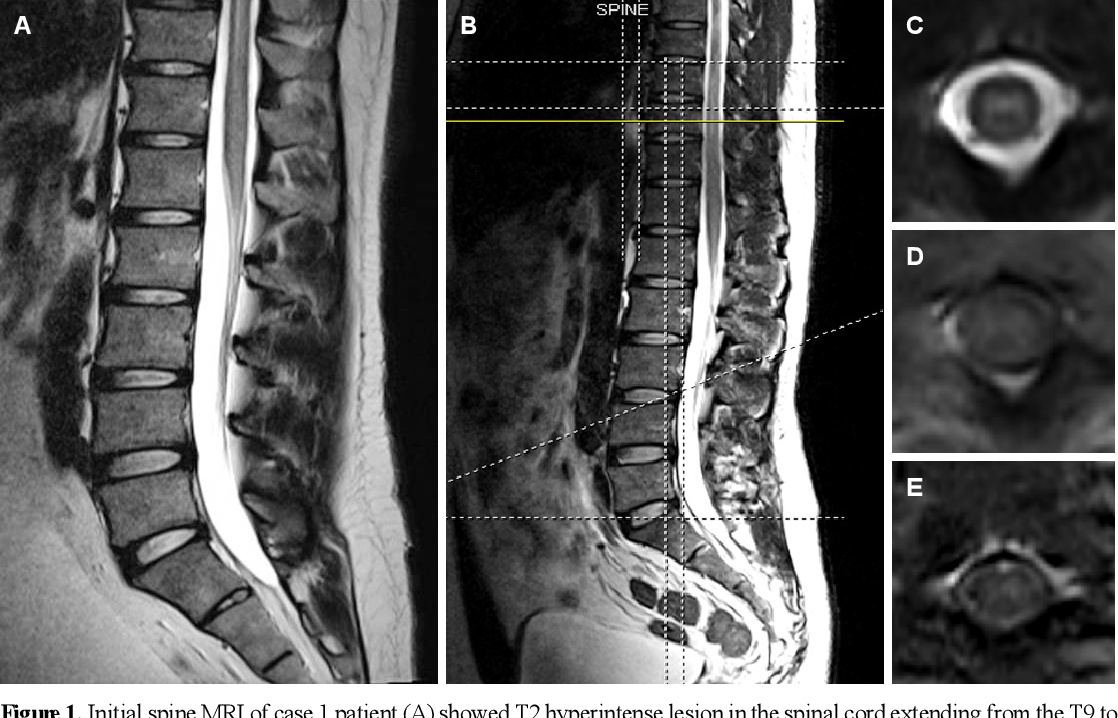

테이크오프 전 보드에 파도가 맞으면서 테일이 들릴 때 허리가 순간적으로 꺾이며 데미지가 생기며 유연성이 부족한 상태에서 그대로 척추에 손상이 생기면서 허리가 망가진다. 척수 혈류 문제로 인해 하반신에 증상이 나타나게 되면 마비로 이어질 수 있다.

2012년 관련 사례들이 발표된 비교적 최신 병증으로, 서퍼들에게 주로 발생하는 비외상성 척수 손상이다. 과신전 중에는 척추로 이어지는 혈관이 꼬여 척수에 산소가 부족해진다. 특히 초보 서퍼들에게서 가장 흔히 볼 수 있는 병이나, 최근 요가 필라테스 등 등을 과도하게 펴는 모든 활동에서 발생한다는 것이 밝혀졌다.